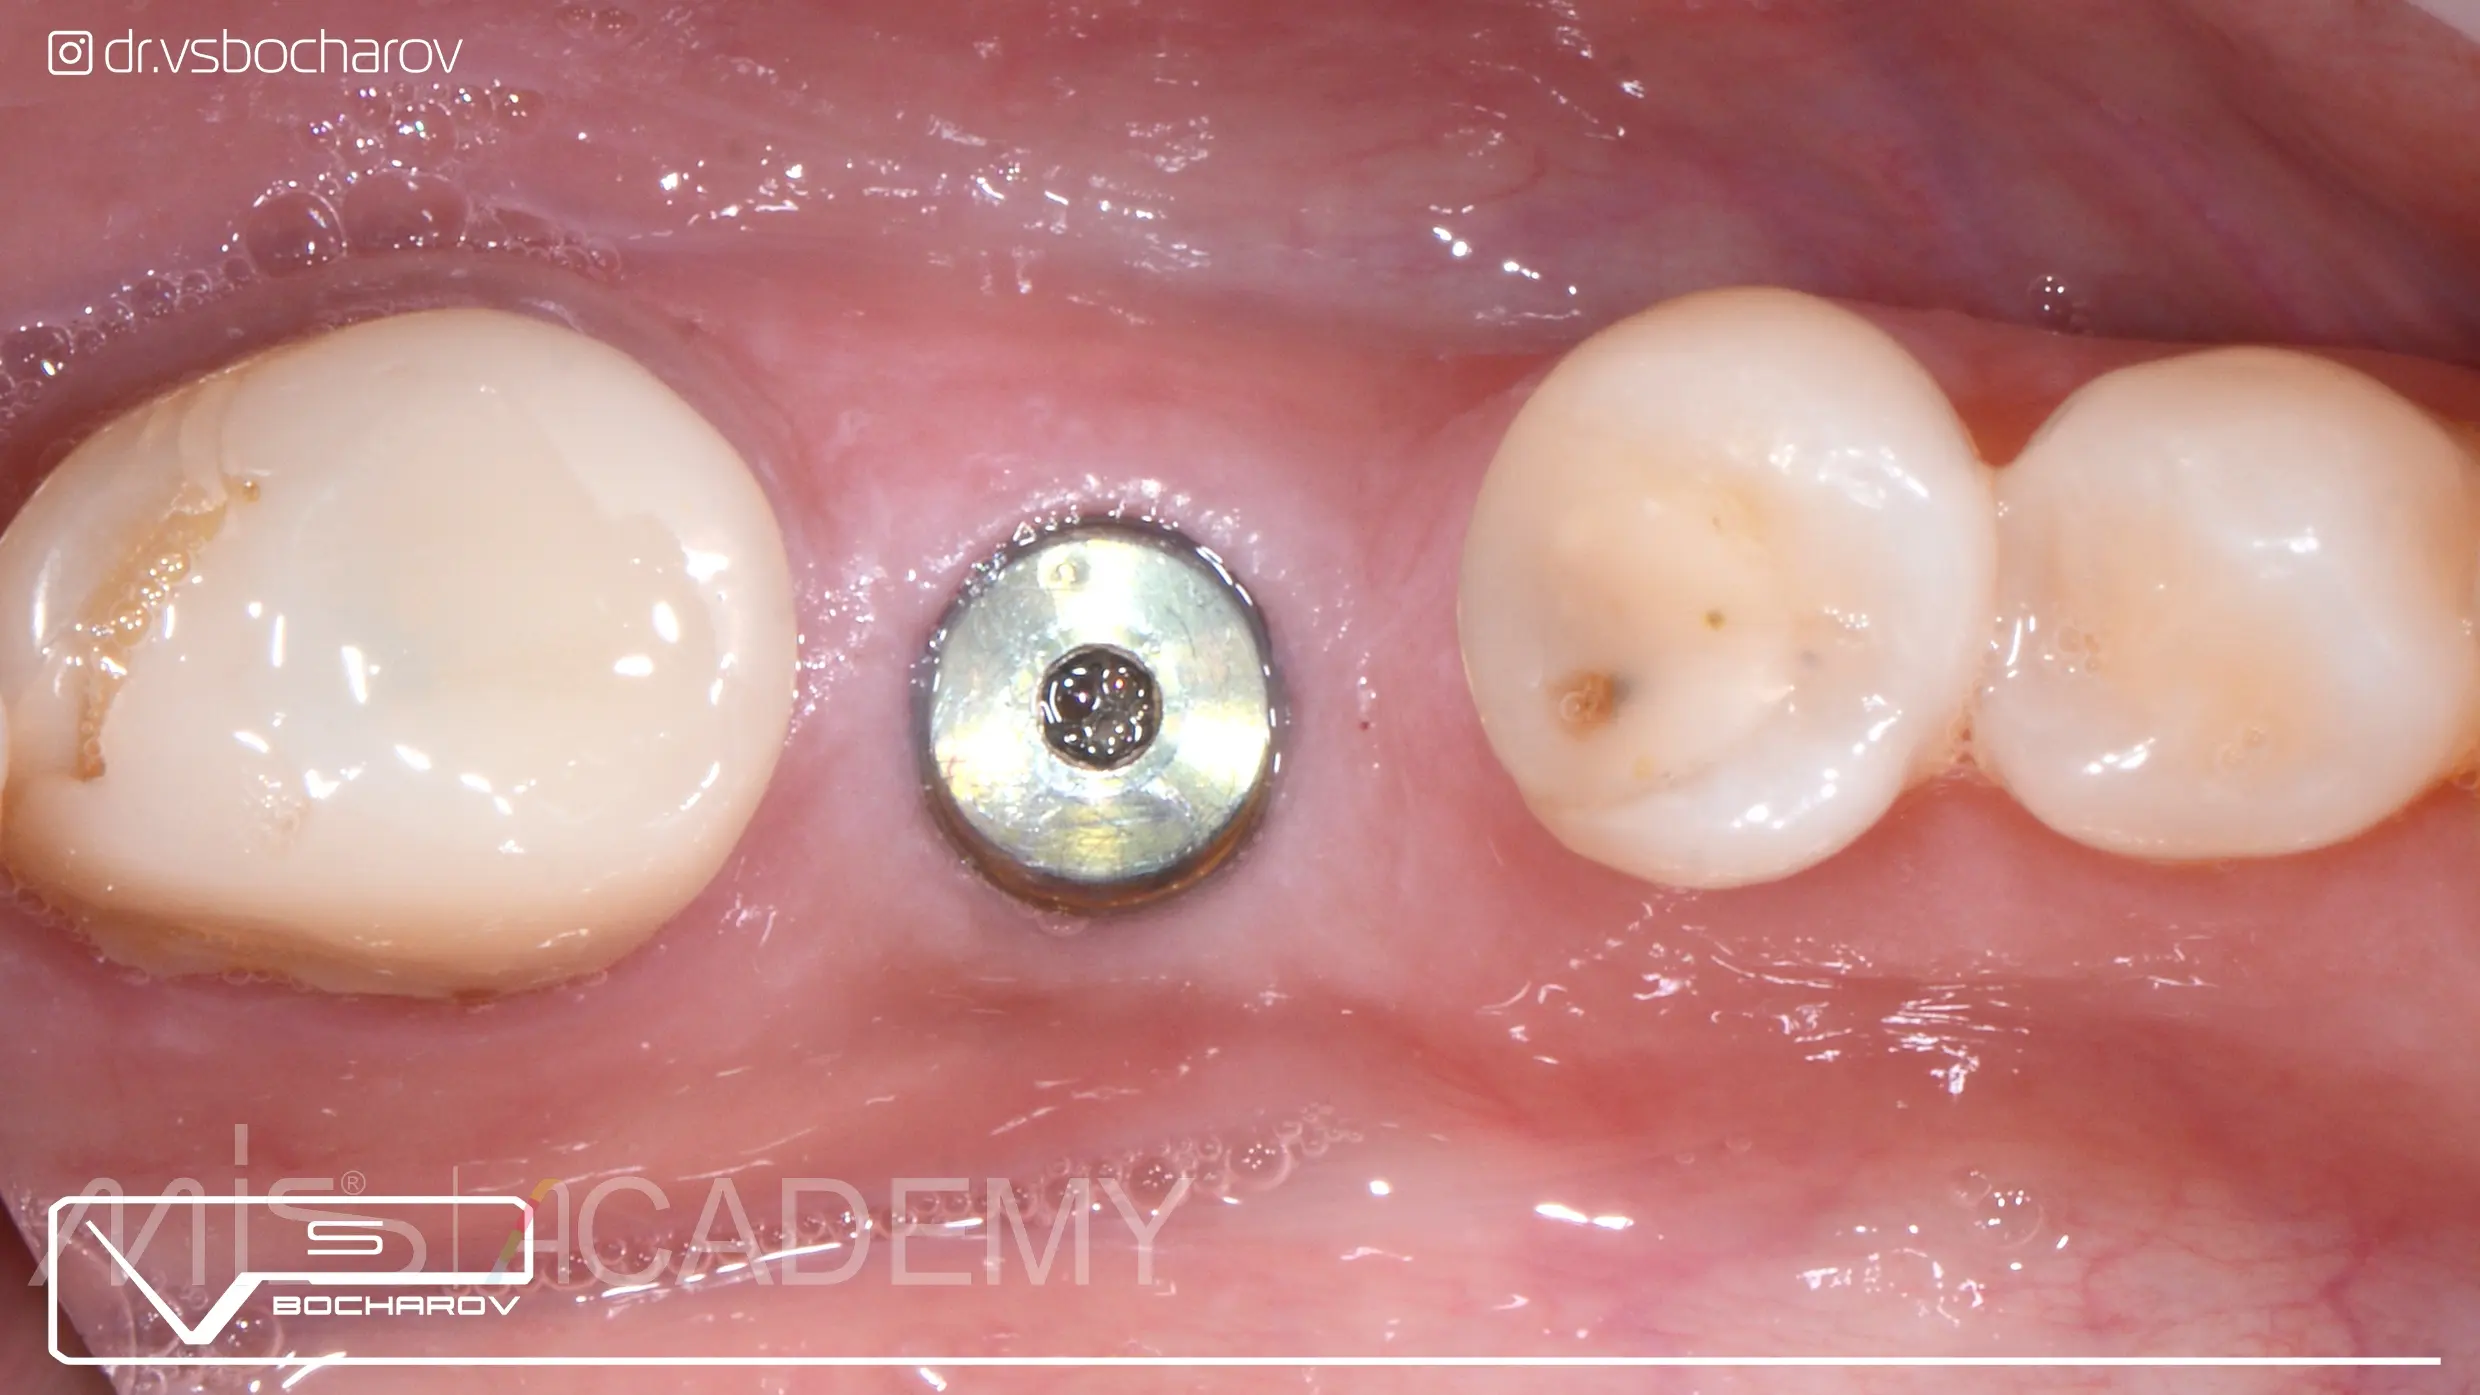

Стандартная работа в области нижней шестерки слева:

— Проведена установка имплантата МИС С1 с одномоментной аугментацией ССТ и установкой формирователя десны.

— Далее провизорное протезирование и постоянная конструкция на цементной фиксации коронки из дисиликата лития на гибридном абатменте.